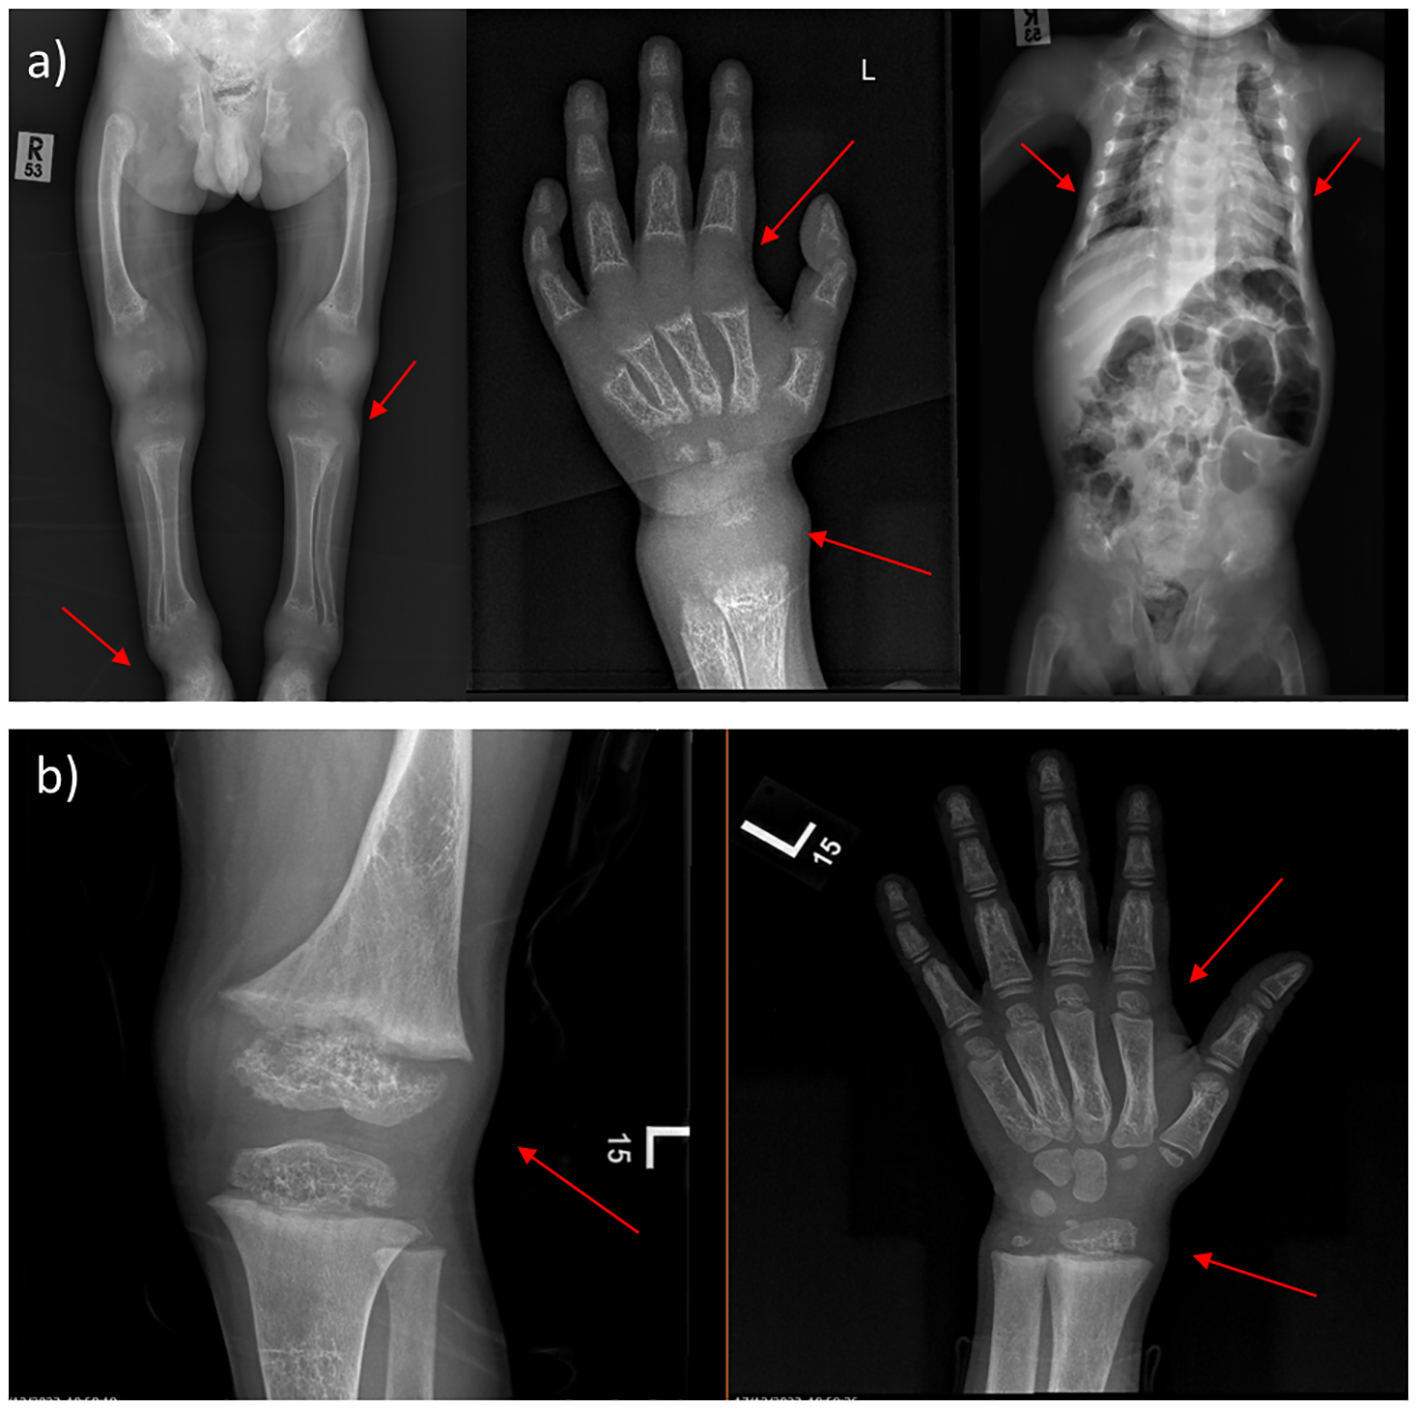

Moreover, the radiological features before and after treatment are shown in (Figure 1). After one year and a half on treatment (6 weeks IV calcium, then maintained on oral calcium 5 gm every 6 hours daily), the images showed interval improvement (Figure 1B) compared to the previously seen growth plate widening and metaphyseal irregularity/fraying (Figure 1A), with interval metaphysical sclerosis in keeping with healing rickets. All patients were confirmed genetically to have HVDDR-II.

X-ray findings of 4-year-old male. (A) Before treatment, the images showing generalized decreased bone density, the profound widening of the growth plate with metaphyseal cupping and fraying of bilateral hips, ankles, knees, and wrists. Narrow chest wall with evidence of significant ricketic changes and costochondral junction fraying. (B) One year and a half after treatment (6 weeks IV calcium, then maintained on oral calcium 5 gm every 6 hours daily); showing interval improvement compared to the previously seen growth plate widening and metaphyseal irregularity/fraying, with interval metaphysical sclerosis in keeping with healing rickets. (Case 2 in the Supplementary File).